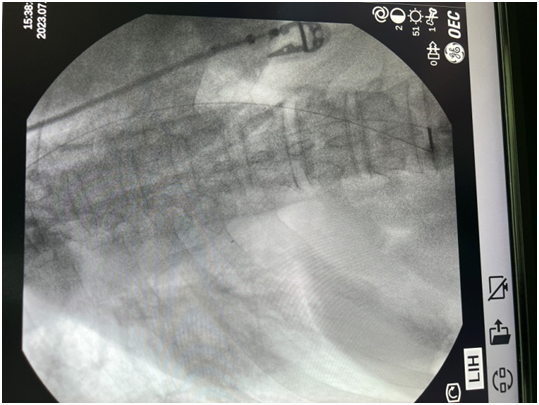

7 月 25 日,经过充分准备、C 型臂定位,在全麻下穿刺针进入蛛网膜下腔退出针芯后,脑脊液回流通畅,植入并固定好导管,在左侧腋前线平肋弓处植入皮下注射装置,缝合微创小伤口,手术完成。